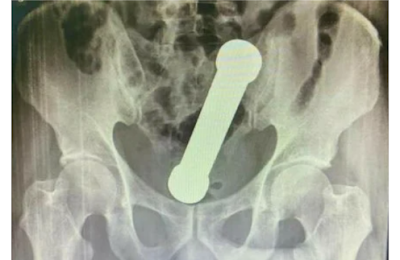

Ao realizarem um exame de raio-X, os médicos encontraram um peso de dois quilos, de cerca de 20 centímetros de comprimento, como os que são usados em academias de ginástica para exercícios de braço, dentro do homem.

O haltere estava entre o reto e o intestino grosso do paciente, que, depois do exame, admitiu ter introduzido o peso de academia no corpo para cumprir sua vontade.